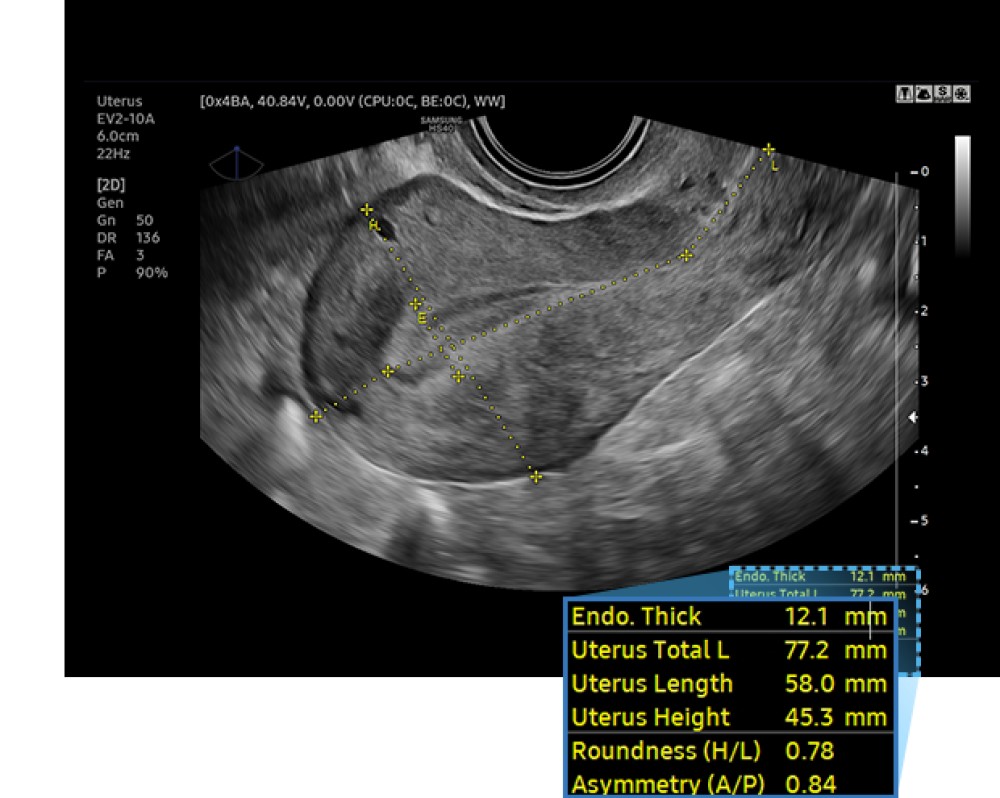

RealisticVue™: Yüksək dəqiqlikli 3D anatomiya təsvirini göstərir, detallar və real dərinlik qavrayışı ilə. İstifadəçi tərəfindən seçilə bilən işıq istiqaməti, daha yaxşı müəyyən edilmiş anatomik strukturlar üçün incə kölgələr yaradır.

Samsung HS40 çoxşaxəli, orta səviyyəli ultrasəs sistemidir və obstetrika, ginekologiya, muskuloskeletal (MSK), abdominal, pediatrik, kiçik orqanlar, urologiya və vaskulyar görüntüləmə daxil olmaqla geniş klinik tətbiqlər üçün yüksək keyfiyyətli təsvir təmin edir. O, diaqnostik etibarlılığı və iş prosesinin səmərəliliyini artırmaq üçün qabaqcıl təsvir texnologiyalarını istifadəçi dostu xüsusiyyətlərlə birləşdirir.